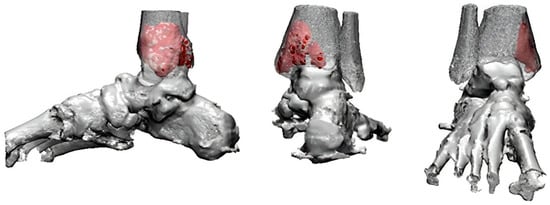

An 81-year-old male presented with left-ankle pain following a fall. The patient had a history of stage-IIA non-small-cell lung carcinoma (NSCLC) treated with intensity-modulated radiation therapy nine months earlier. Preoperative imaging revealed a lytic lesion with cortical thinning and a fracture line in the distal third of the fibular shaft (Figure 9A,B). MRI revealed a 3.5 cm lobulated mass with central necrosis and prominent extraosseous extension. The signal characteristics were consistent with metastatic disease, as demonstrated via T2-weighted imaging showing a hypointense lobulated mass with irregular margins and through contrast-enhanced T1-weighted imaging displaying heterogeneous intermediate-to-low signal intensity with central necrotic areas and extraosseous extension (Figure 9C). Based on the imaging results and clinical history, the lesion was diagnosed as a pathological fracture secondary to metastatic lung cancer.

Figure 9. Preoperative imaging. (A) Preoperative X-ray showing a lytic lesion in the distal third of the fibula with cortical thinning and a visible fracture line. (B) Preoperative CT scan illustrating the lesion’s cortical destruction, dimensions, and evidence of a pathological fracture. (C) Preoperative MRI. (a) T2-weighted image demonstrating a hypointense lobulated mass with irregular margins. (b) Contrast-enhanced T1-weighted image showing heterogeneous intermediate-to-low signal intensity with central necrotic areas and prominent extraosseous extension.